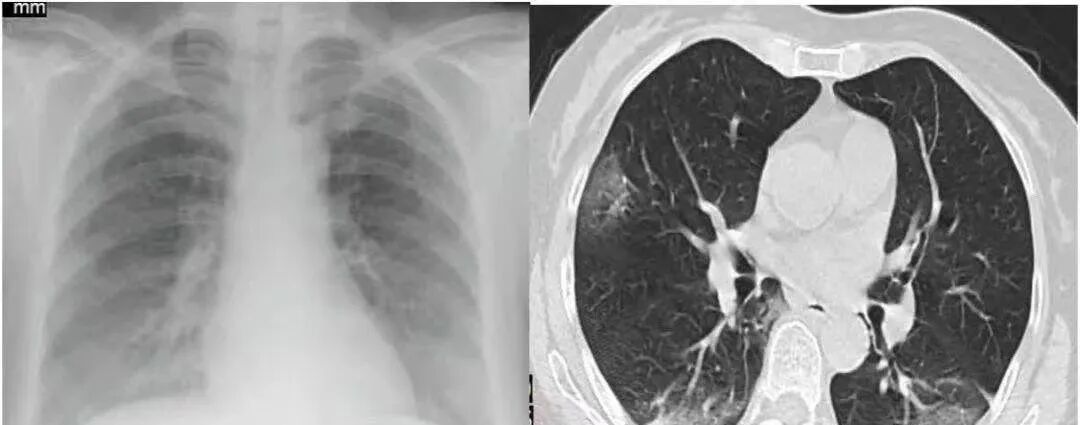

对此,建议痊愈的患者,应该给自己安排一个后续病情追踪,才不怕自己的健康被潜在危害杀个措手不及!检查肺部损伤:新冠病毒曾经影响过肺部健康以及呼吸道,所以患者康复后仍会有咳嗽、呼吸困难等状况。所以应安排一个肺部CT,新冠肺炎特征为以肺外周分布为主的肺多发磨玻璃阴影或者实变影,后期可出现肺纤维化病变,肺CT能够准确判断新冠肺炎是否对肺部造成伤害和遗留问题等。